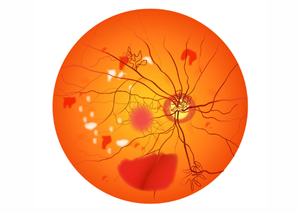

Діабетична ретинопатія

Діабетична ретинопатія — це ускладнення діабету, яке вражає сітківку ока (шар тканини, що вистилає внутрішню частину ока і відповідає за сприйняття світла).

Перейти до послуги